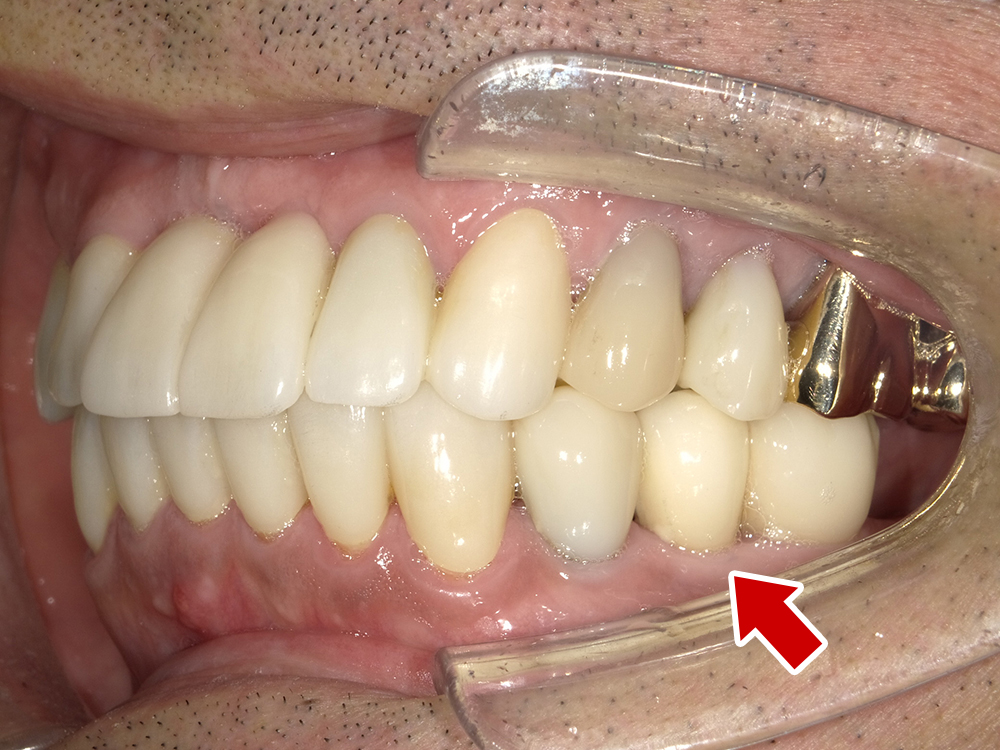

58歳 男性 歯科医療関係者紹介

- 主訴

- 右下を抜歯して噛めない

- 処置内容

- インプラント2本埋入

- 治療費用

- 約80万円(税込)

- 治療期間

-

8か月

仮歯完成まで5か月(この時点で噛めます)、+3か月で最終素材へ

- リスク

- 上部構造物、仮歯の破折、術後の腫れ(3日)、人工歯根脱落リスクがあります